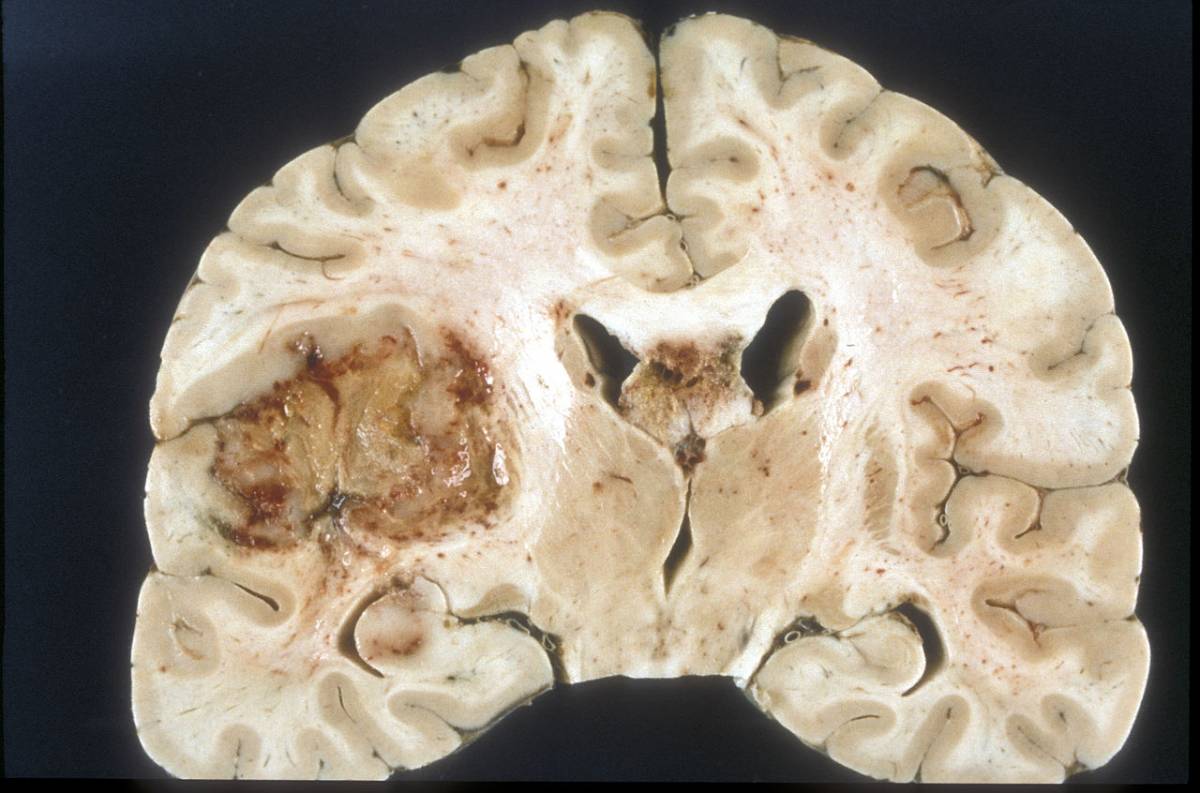

tumore al cervello

glioblastoma